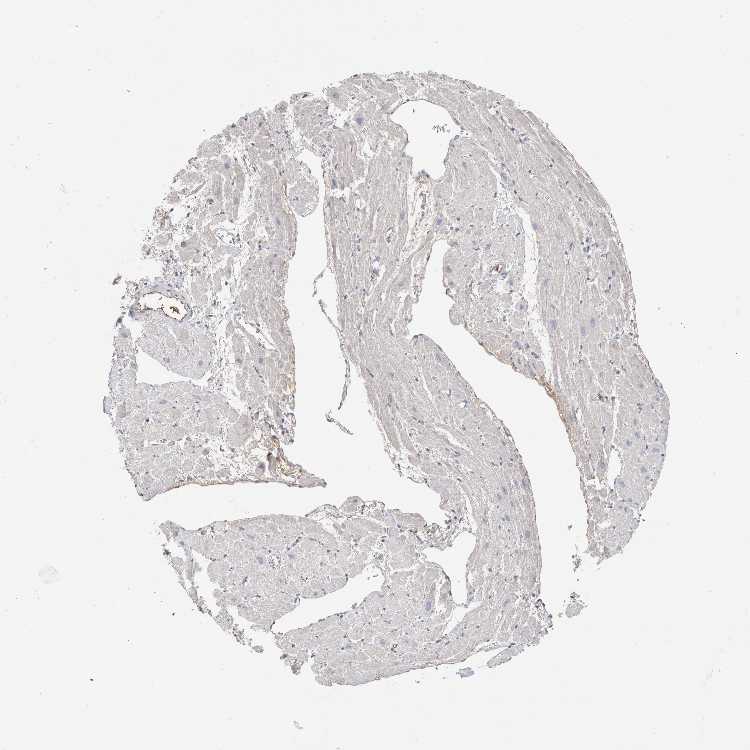

HEART MUSCLE - Antibody stainingi

Antibody staining in the annotated cell types in the current human tissue is reported as not detected, low, medium, or high, based on conventional immunohistochemistry profiling in selected tissues. This score is based on the combination of the staining intensity and fraction of stained cells.

Each image is clickable and will lead to virtual microscopy that enables deeper exploration of all samples and also displays staining intensity scores, fraction scores and subcellular localization as well as patient and tissue information for each sample.

Antibody HPA031828Antibody CAB025686

Cardiomyocytes Not detectedNot detected